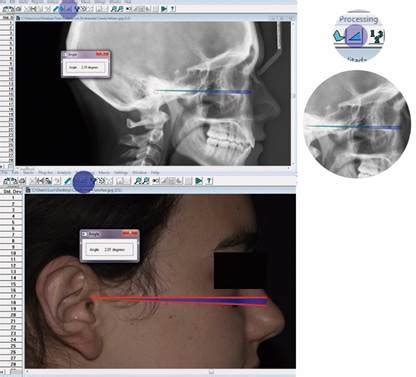

Cole definió la posición natural de la cabeza (natural head position, NHP) como la relación de la cabeza con respecto a la vertical verdadera, y la postura natural de la cabeza como la relación entre la cabeza y las vértebras cervicales. En tanto que magnitud reproducible, posibilita comparaciones racionales entre diversos estadios de tratamiento en el mismo paciente y comparaciones cefalométricas racionales entre pacientes.

La posición natural de la cabeza se establece ya en etapas tempranas de la vida. Se ve influida por los requisitos del equilibrio (conductos del oído medio vestibulares) y de la capacidad visual (eje facial horizontal), así como por la propiocepción de las articulaciones y la musculatura en postura erguida. Es más constante en comparación con otras líneas de referencia dentro del cráneo.

La principal innovación en el diagnóstico facial data de 1978. En ese año, Jacobs modificó el análisis de González-Ulloa y trazó un plano de referencia vertical auténtico a través de la subnasal (Sn). Esta magnitud de medida se obtiene mediante una plomada suspendida libremente del techo. También los artistas renacentistas italianos trabajaban con líneas de fuerza de gravedad similares, para así posicionar la cabeza de sus modelos para cuadros de perfil.

Los autores utilizan la posición natural de la cabeza como ayuda orientativa durante evaluaciones fotográficas de proporciones faciales, así como para la realización y la evaluación de radiografías cefalométricas. A fin de determinar la posición natural de la cabeza, se pide al paciente sentado que mantenga la cabeza recta y mire un espejo situado directamente delante, con los pies ligeramente separados y los brazos colgando. Tanto los labios como la musculatura maxilar y de la nuca deberían estar relajados.

Posición natural de la cabeza para una evaluación precisa.